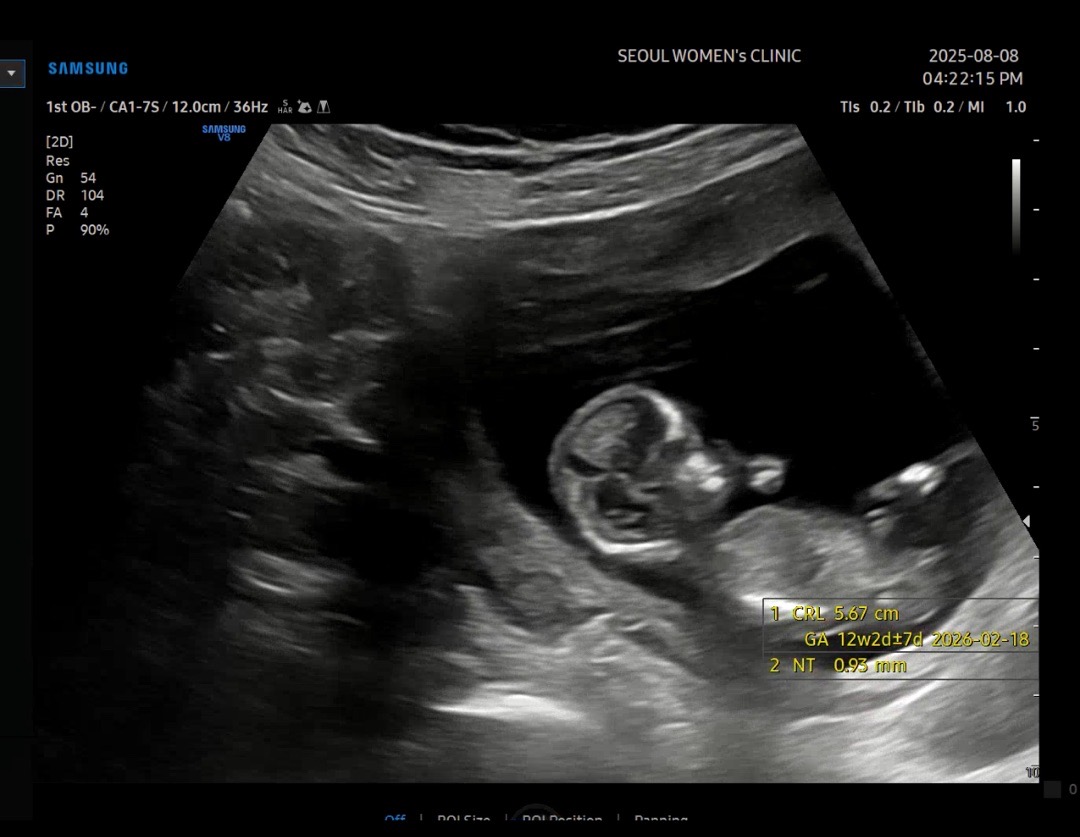

12주 1일입니다 각도법 고수님들 도와주세요!

가만히 있지를 않아서 최대한 옆모습으로 가만히 있는 모습인데 성별 알수 있을까요...? 넘나 궁금해서요,,ㅎㅎ